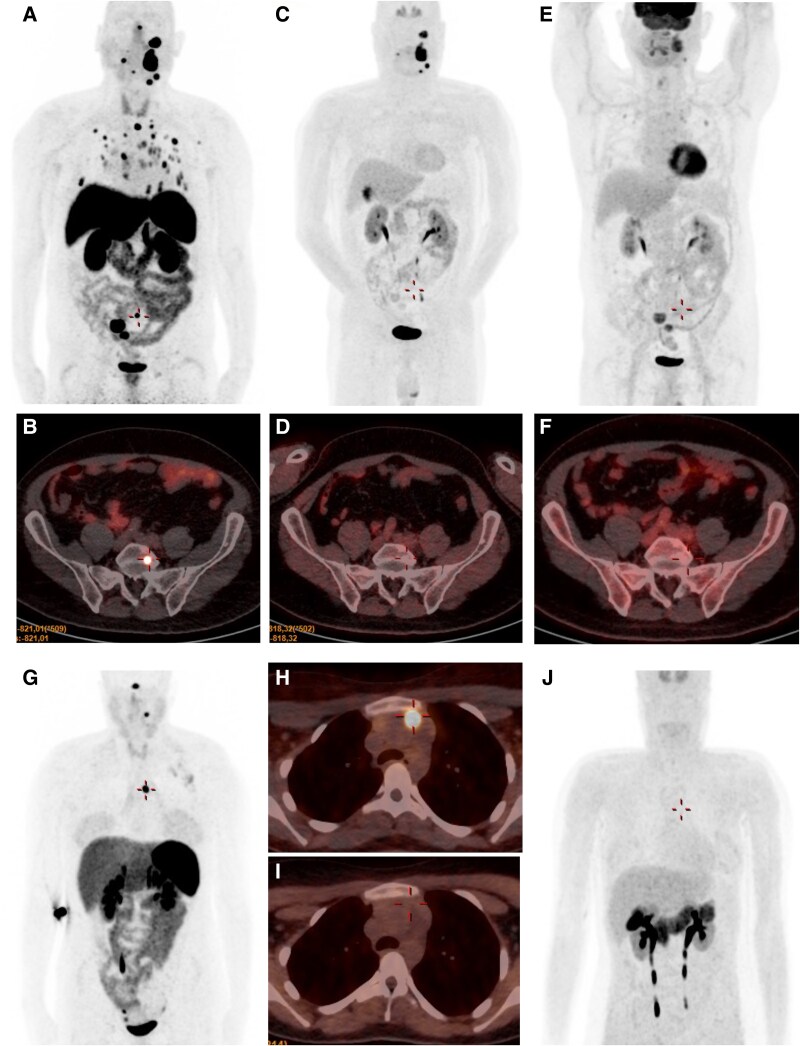

Methods: A total of 56 individuals with the p.(Gly78Arg) variant in the SDHAF2 gene were prospectively evaluated. Of the 33 subjects who developed paragangliomas (PGLs)/pheochromocytomas (PCs) throughout follow-up, clinical, biochemical, and imaging data were collected. [68Ga]Ga-DOTA-TOC and [18F]DOPA positron emission tomography/computed tomography (PET/CT) scans were carried out on a subset of 22 patients with PGLs/PCs to compare their accuracy; surgical specimens (n = 13) were microscopically evaluated to elucidate their potential malignant behavior.

Results: Of the 33 patients (58.9%) with SDHAF2-related tumors, 17 (51.5%) were women, with a mean age at diagnosis of 38.6 ± 17.2 years. Tumor development was found to be inherited paternally in all subjects. All the patients evaluated except 1 showed head and neck PGLs. Eleven patients (33.3%) showed mediastinal and abdominal extra-adrenal PGLs and 2 patients presented PCs. Multifocality was observed in 26 subjects (78.8%). Sixteen patients (48.5%) were asymptomatic at diagnosis. Only 4 patients with PGLs/PCs showed normetanephrine or 3-methoxytyramine secretion. Metastatic disease was observed in 2 patients (6.1%). Grading System for Adrenal Pheochromocytoma and Paraganglioma score was ≥3 in 84.6% of tumors and Pheochromocytoma of the Adrenal Gland Scaled Score was ≥4 in 69.2%. [68Ga]Ga-DOTA-TOC PET/CT showed a greater detection rate (95.7%) of multifocal PGLs and metastatic lesions than [18F]DOPA PET/CT (79.3%), as well as higher mean maximum standardized uptake value.

Conclusion: The current study offers new insights into the phenotypic characterization of SDHAF2-related paraganglioma syndrome including the development of extra-cervical PGLs and metastatic transformation.